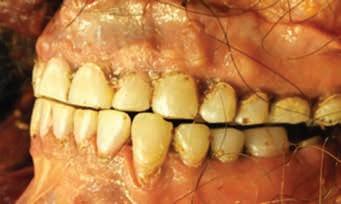

Dental Evidence Recovered: Maxilla and Mandible.

Frontal View

Right Left

Right Lateral View

Left Lateral View

Right Left Right Left

Maxilla

Mandible